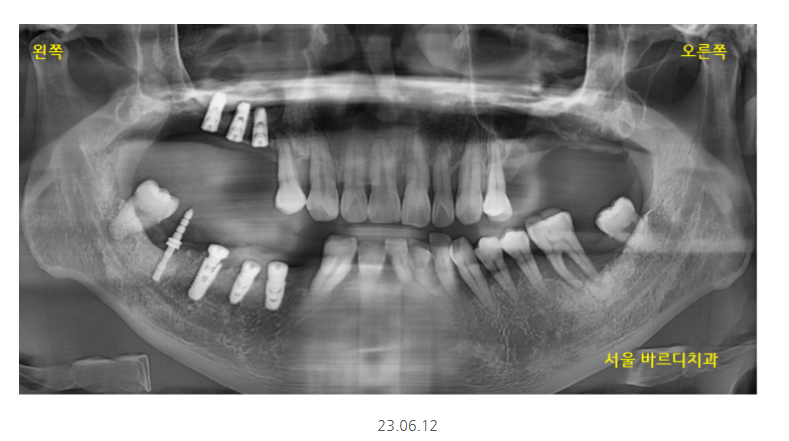

환자분처럼 양쪽 어금니가 다 없고

임플란트 뼈이식을 많이 해야할경우

안전하게 나눠서 임플란트 수술을 진행합니다.

환자분은 왼쪽이 많이 불편하시다 하셔서

1순위로 반영하여 수술해드렸는데요.

(언제나 환자분의 요구사항이 1순위 반영사항입니다)

잇몸뼈가 많이 없는 상악의 경우

발치 후 뼈이식 하고 기다리다

임플란트를 심기도 하였습니다.

임플란트 뼈이식 흡연으로

충분히 기다렸습니다.

5월달에 왼쪽 위부터 수술했는데